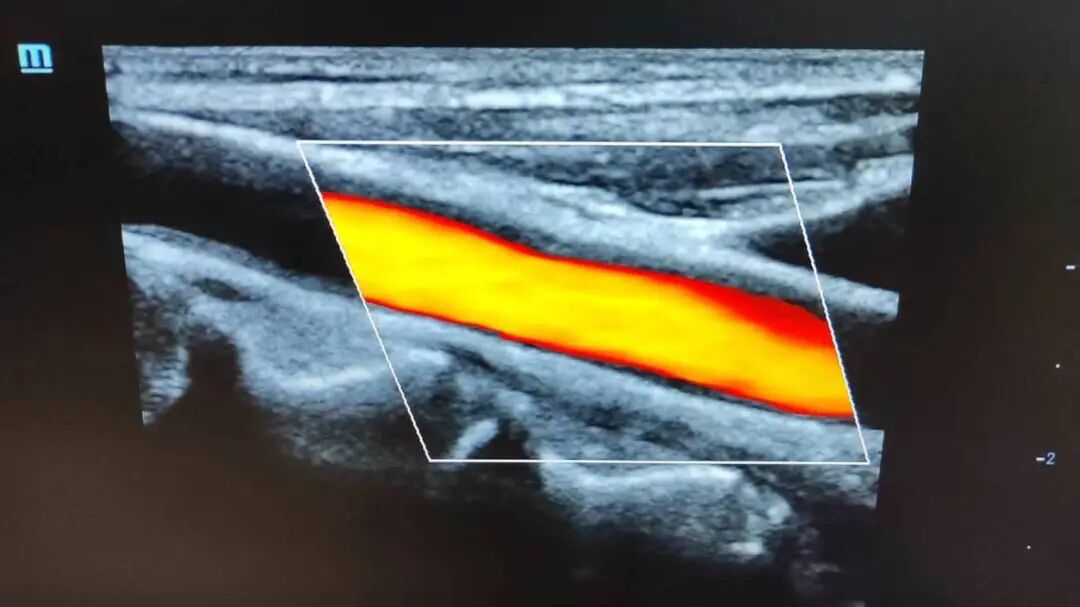

夏医生先为他完成心脏超声检查,结果提示心功能减低伴少量心包积液。随后,她又对东哥双下肢血管进行了细致全面、反复认真的探查,明确血管通畅,排除了血管病变导致肿痛的可能。她一边检查一边温柔地告知东哥:“您别担心,下肢血管是通畅的,腿脚肿胀属于暂时症状,接下来只要在内分泌科规范治疗、控制好血糖,积极预防并发症,身体会慢慢好转的,您要相信医生,更要相信自己。”

▲血管超声图